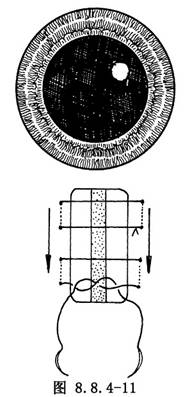

縫針在鞏膜內穿行路線見圖8.8.4-9。過淺鞏膜容易豁開,過深容易造成穿透。因此,操作時應將眼球固定牢靠,持針的手要穩,緩緩用力,當針尖刺入達到深度後,平行鞏膜進針約3~4mm出針,每對縫線之間的距離爲5mm左右。縫針方向與加壓物的擺放方向一致,即加壓物與角膜緣平行,縫針方向也與角膜緣平行(圖8.8.4-10);加壓物與角膜緣垂直,縫針也垂直(圖8.8.4-11)。

鞏膜外加壓物一般採用非吸收材料。臨牀上使用最多的是7mm寬的硅膠輪胎和硅海綿,能夠頂壓住常見的3mm以下的裂孔(≤2個視乳頭直徑)。如果裂孔較大,就需要更寬些的加壓物。對於大的馬蹄形裂孔,有時加壓物與角膜緣平行放置,雖然能形成較寬的鞏膜嵴,但裂孔呈魚嘴狀張開,視網膜會形成放射狀皺褶,牽拉裂孔後脣,因而發生漏水。此時把加壓物改爲放射狀放置,可減少這種情況發生。